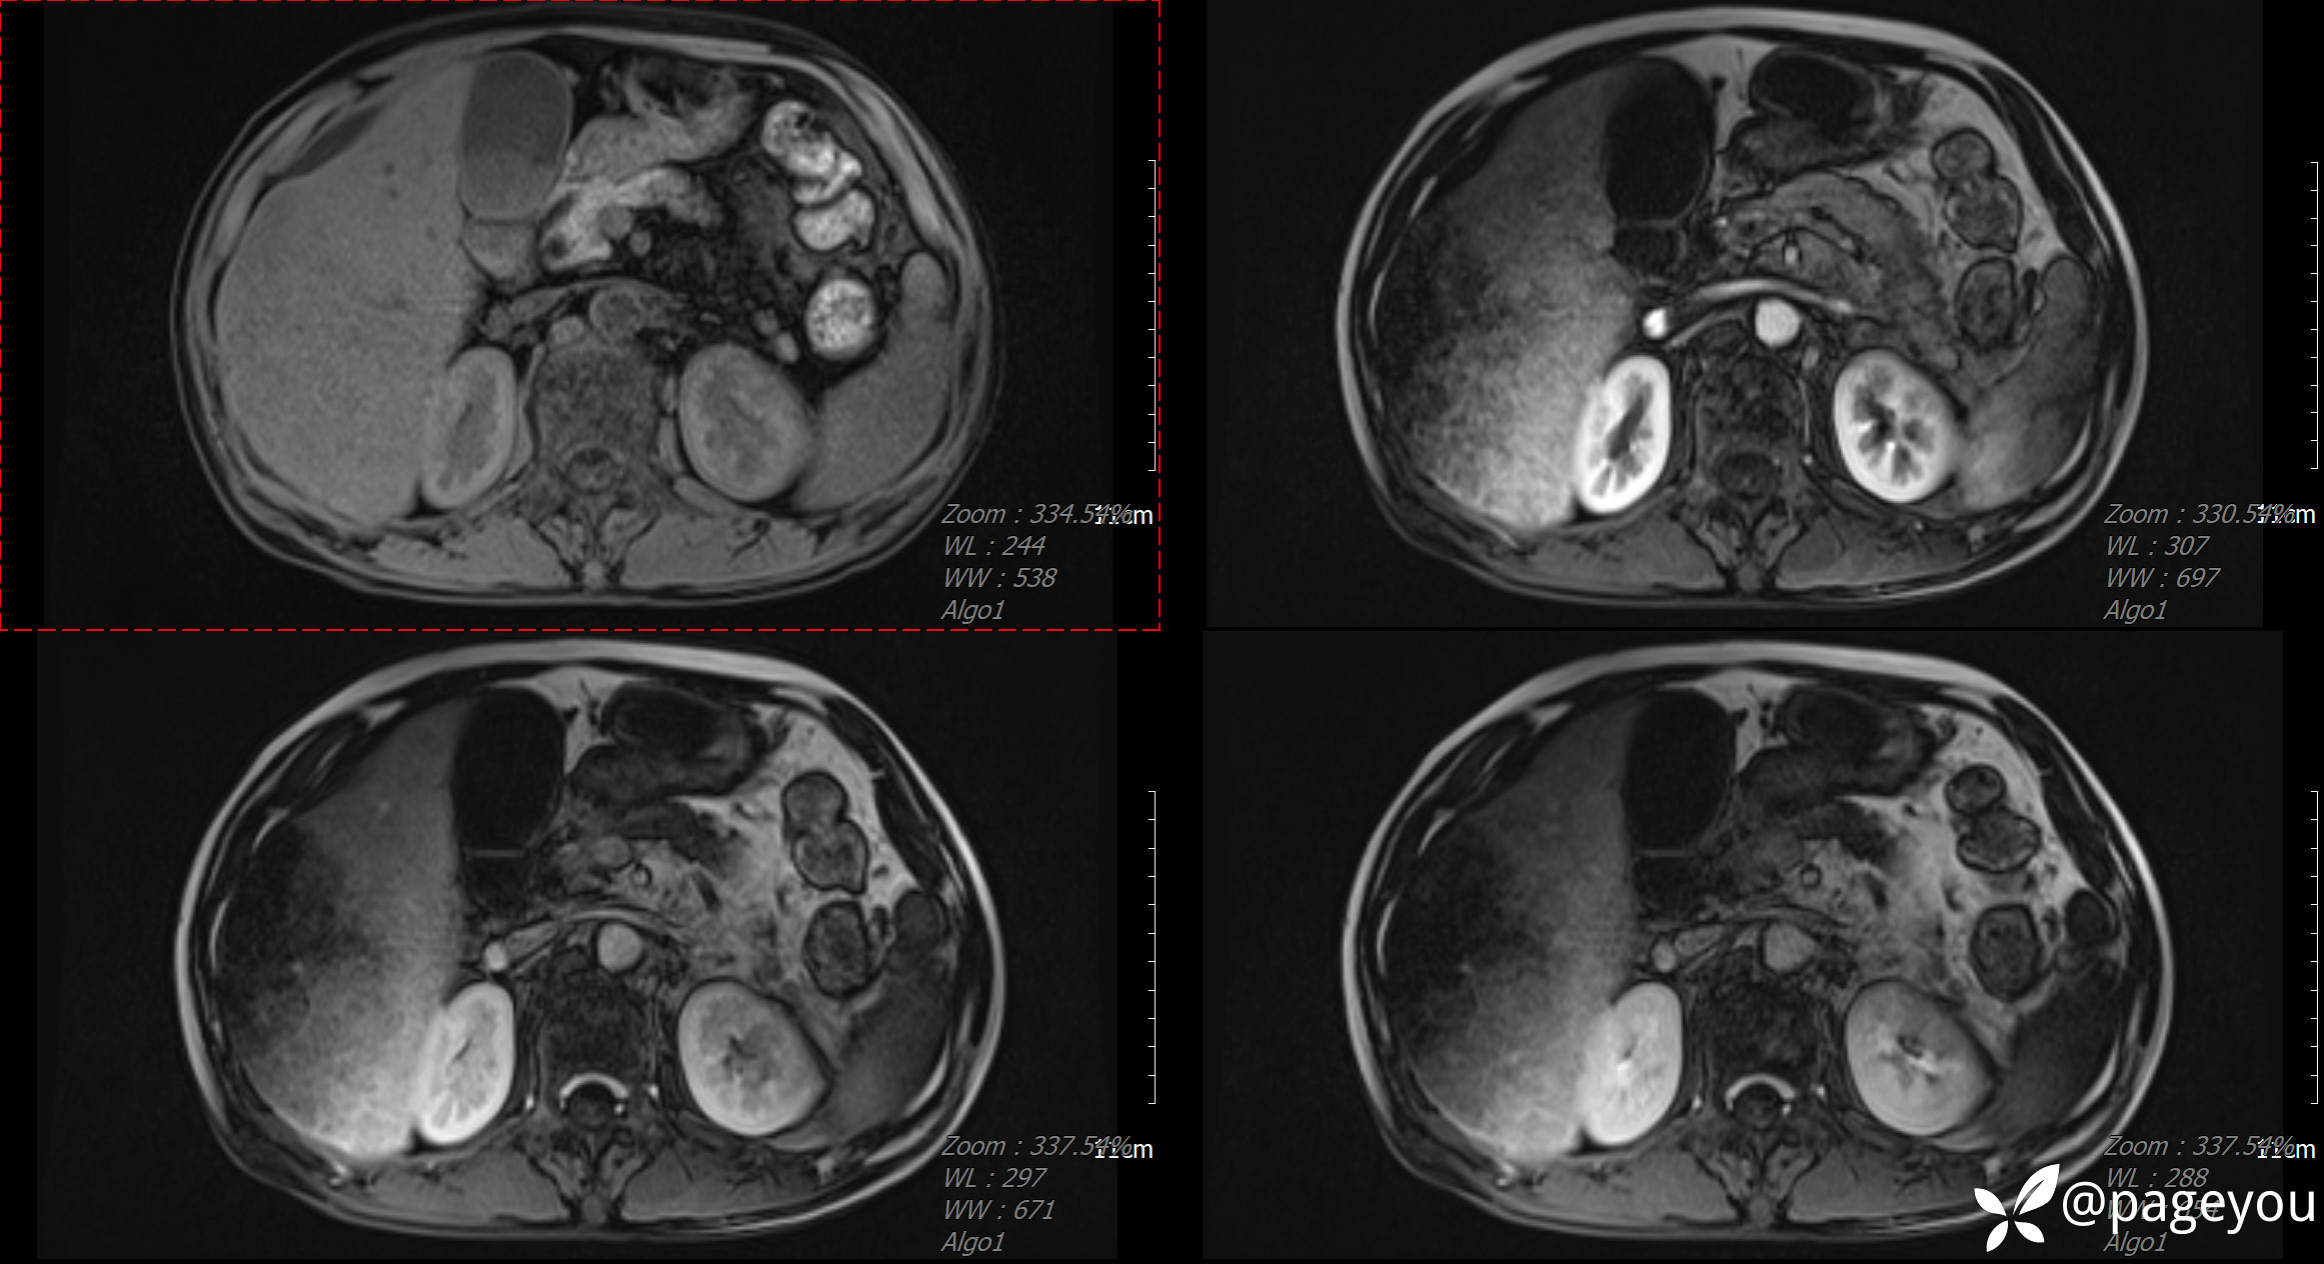

MRI检查: